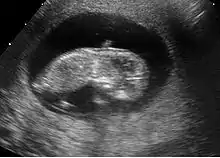

Embryon à 8 semaines

L'embryon mesure entre 15 et 22 mm. La vésicule vitelline qui le nourrit est juste à côté. À la fin de cette semaine, les coudes deviennent visibles